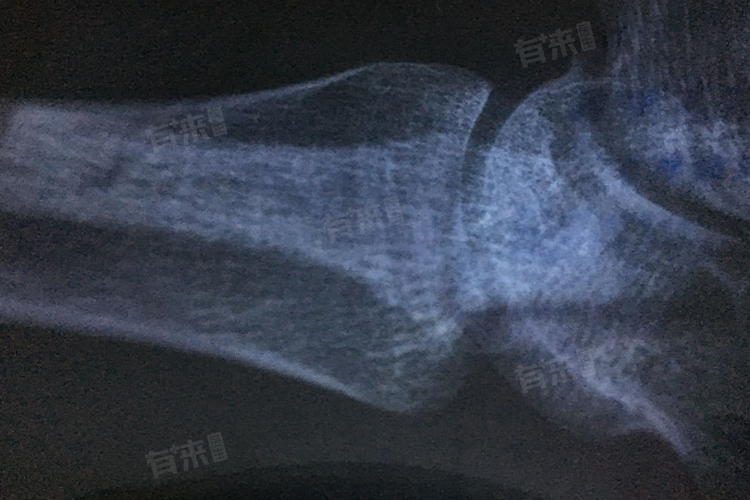

- 影像学检查:最常用的方法是拍摄左手手腕部的X线片,通过观察X线影像中手腕部骨骼的形态、骨骺与骨干的融合程度来判断。若骨骺线完全消失,骨干与骨骺紧密相连,基本可确定骨龄闭合。

- 骨龄评分法:医生依据特定的骨龄评分系统,对X线片上手腕部各块骨骼的发育阶段进行评分。当评分达到对应年龄段骨龄闭合的标准分值时,可辅助判断骨龄闭合情况。